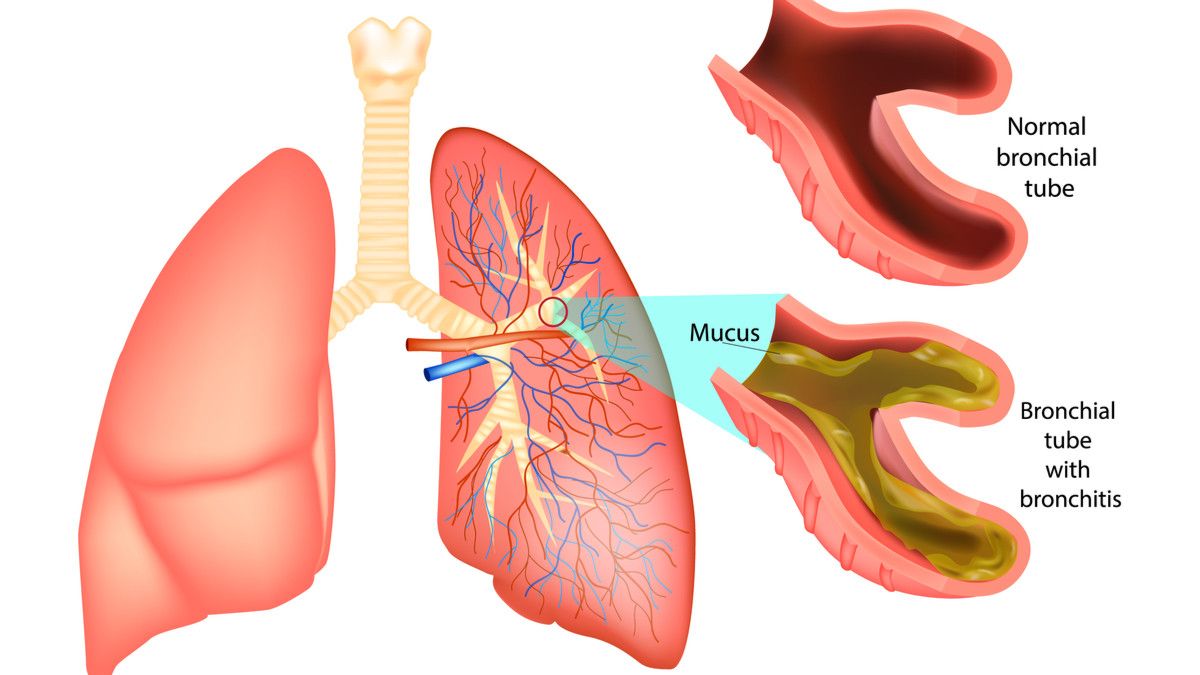

Bronkitis Definisi Gejala Penyebab Hingga Pengobatan

Mengenal Bronkitis Rsud Dr Abdul Aziz

Bronkitis Gejala Penyebab Dan Pengobatan Halodoc

Bronkitis Gejala Penyebab Komplikasi Hingga Pengobatannya Orami